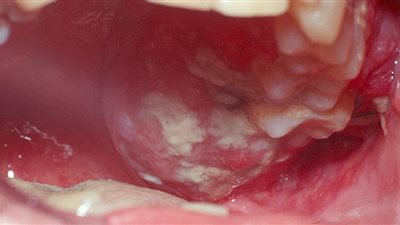

اعراض سرطان الفم

أعراض تكشف إصابتك بسرطان الفم.. طبيبة تحذر من تجاهلها

أنواع سرطان الفم من الخفيفة إلى الخطيرة

6 أسباب رئيسية تشير إلى إصابتك بسرطان الفم

منها صعوبة البلع والنزيف.. أعراض سرطان الفم

ما هو سرطان الفم وأشهر أعراضه

ما هي مسببات سرطان الفم؟